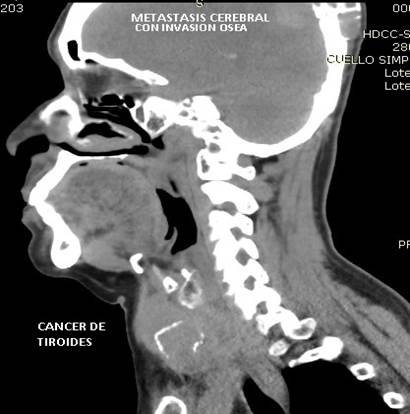

CASO 2 (METASTASIS CEREBRAL)

Paciente de 68 años de edad, que ingresa referida de otra institución por presentar más tumoral en región occipital derecha de gran tamaño dura muy adherida, dolorosa con circulación colateral; paciente desorientada en tiempo y espacio, irritable y poco colaborativa, en algunas ocasiones ha presentado convulsiones tónico clónicas. Además, presenta masa cervical voluminosa, a nivel tiroidea, dura, adherida a estructura aéreas y vasculares.

Se toma biopsia con aguja gruesa de lesión tumoral cervical y tumoración occipital encontrando carcinoma papilar variante oncocitica.  Paciente fue tratada por el departamento de oncología clínica en forma paliativa y con Sorafenib por no haber mejoría con radio-yodo.

Ilustración 7 Ca de tiroides vultuoso

Fuente: Hospital de Especialidades Guayaquil “Doctor Abel Gilbert Pontón”.

Autor: Dr. Fernando Moncayo A.

Ilustración 8 Ca de tiroides y metástasis cerebral.